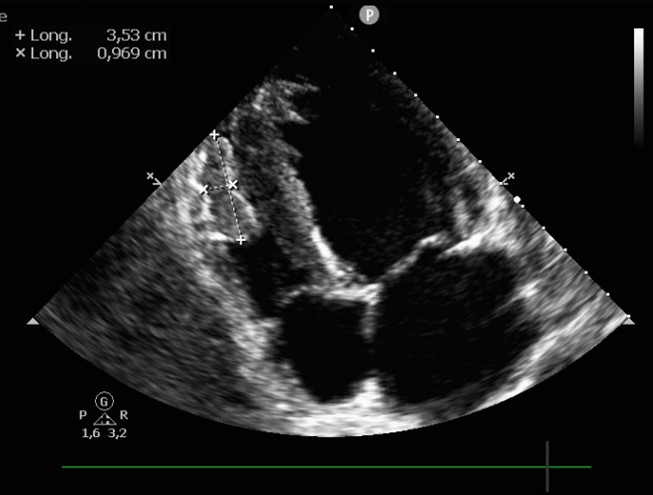

A cardiac ultrasound showed reduced contractility of the left ventricle, with left ventricular ejection fraction (LVEF) of 38% , global longitudinal strain (GLS) of -12% (Figure 2), along with significant spontaneous contrast and dilated left atrium. Additionally, two masses were identified at the apex of the left ventricle (LV) (Figure 3), and a third, larger mass was attached to the lateral wall of the right ventricle (RV) (Figure 4). The appearance of these masses was highly suggestive of thrombus, thus anticoagulation treatment was initiated.

Figure 4: Four-chamber view showing a thrombus at the lateral wall of the right ventricle.